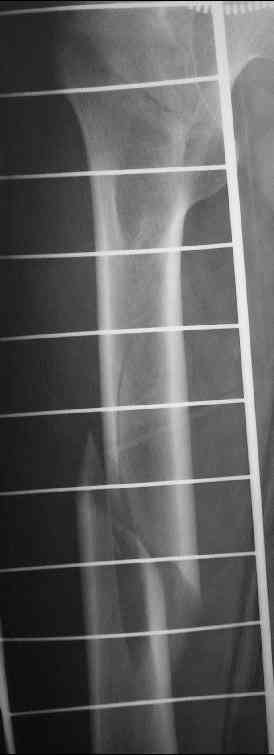

сложный перелом правого бедра

Уважаемые коллеги, пару дней назад к нам поступил пациент 54 лет с таким вот переломом правого бедра.

Сейчас на скелетном вытяжении. Хотелось бы услышать мнения по поводу природы округлого просветления в подвербельной области (аневризмальная киста?)и тактики лечения.

a few days ago a 54 y.o. patient was admitted to our hospital with this fracture of the right femur. Now he is on a skeletal traction. I'd appreciate your opinion as to:

1.the nature of a lucent lesion (?) in subtrochanteric area - is it ABC?

2.treatment options. Thanks,